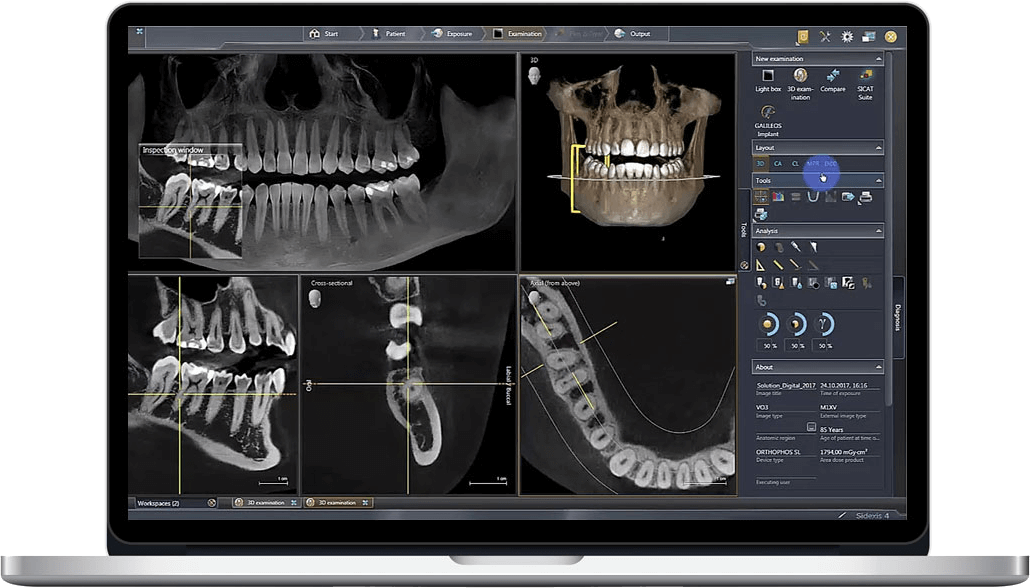

- Diagnostic Acquisition: CBCT scan (0.076-0.12mm voxel) performed at point-of-care with AI-assisted positioning (e.g., Planmeca ProFace+, Carestream CS 9600 AI).

- Surgical/Prosthetic Fusion: DICOM data merged with intraoral scan (IOS) in CAD software. Enables immediate visualization of bone-to-restoration relationships for same-day decisions.

- Automated Segmentation: AI-driven tissue separation (bone, nerves, mucosa) using tools like Materialise Mimics Innovation Suite, reducing manual segmentation time by 70%.

- Hybrid Model Generation: CBCT bone structure + IOS soft tissue merged into single virtual model for crown/bridge, denture, or implant cases.